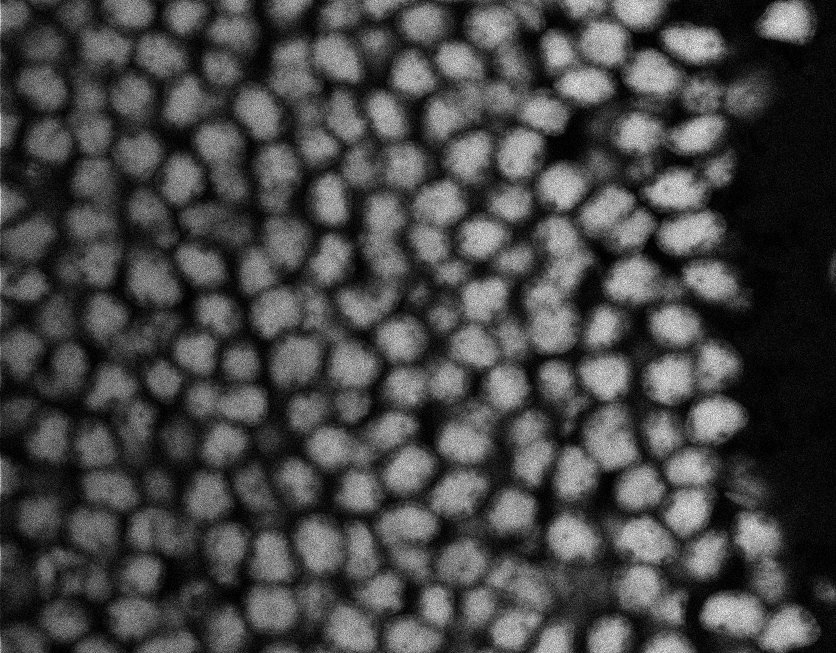

Nuclei

Nuclei - Bis

Nuclei - Bip

Nuclei - Bipolar